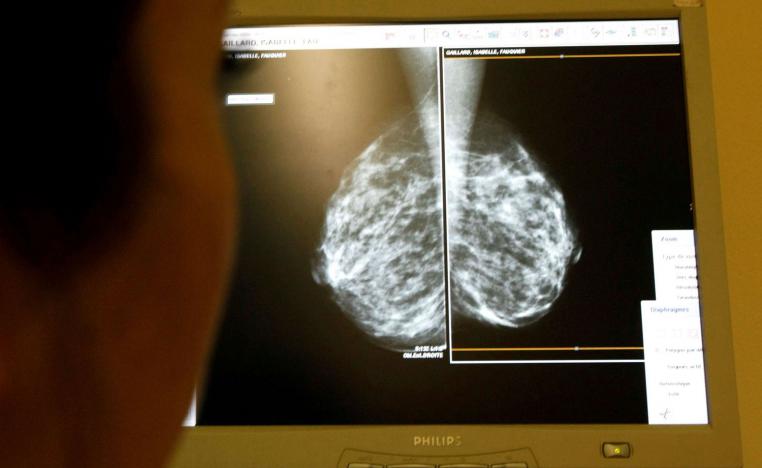

علاج إشعاعي مقتضب يتخطى بنجاح امتحان سرطان الثدي

سرطان الثدي يتصدر الأورام الخبيثة الأكثر انتشارا عالميا